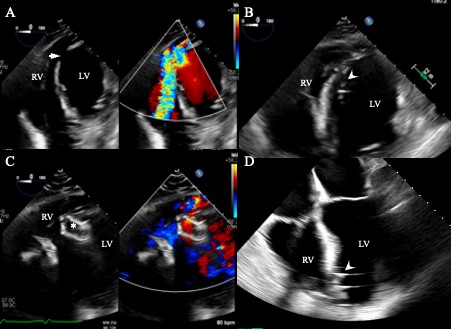

A 49-year-old man presented late with an anterior wall myocardial infarction (MI) status post-primary coronary intervention of the left anterior descending artery that resulted in no reflow of the vessel. The patient was transferred to our institution in cardiogenic shock. His course was complicated with cardiac arrest, for which he had veno-arterial extracorporeal membrane oxygenation placement and decannulation 20 days later. He was noted to have a large apical VSD 48 days after his presentation, with significant left to right shunt on transesophageal echocardiogram (TEE) (Figure 1A). Computed tomography (CT) angiogram showed the VSD measured 2.8 cm x 1.6 cm. The patient underwent successful percutaneous closure of the defect using a 48 mm GCA on day 56 post-MI (Figures 1, 2). A veno-arterial (right internal jugular vein-femoral artery) wire loop was used to cross the VSD, as described in a previous study.1 The initial attempt with deployment of a 24 mm Amplatzer Post-infarct Muscular VSD Occluder (largest available size) (Abbott), was unsuccessful due to misalignment with the apical septum; oblique positioning across the VSD with protrusion of the left ventricular disc towards the right ventricle resulted in an incomplete seal (Figures 1C, 2C) and risk of embolization. A 48 mm atrial septal defect GCA was chosen and successfully deployed through a 14 French (Fr) GORE DrySeal sheath (Figure 1D, 2D) with trace residual shunt.